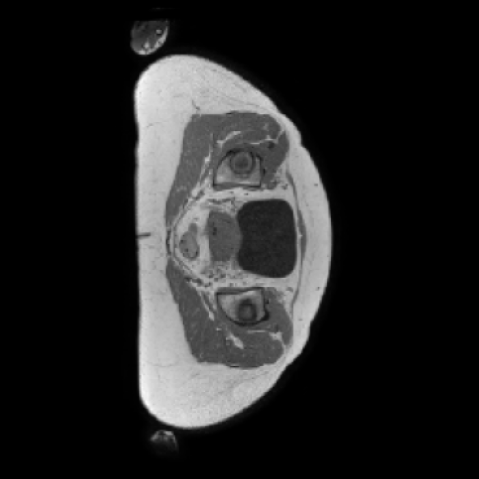

4.4 Med-LSDM outperform 2D SegGuidedDiff Model

We conduct a comprehensive evaluation of our proposed Med-LSDM model against the SegGuidedDiff baseline across three public datasets: AutoPET, SynthRAD2023, and Duke Breast. To do this, we compute multiple quantitative metrics that measure image fidelity and structural similarity between Real images from the original datasets, and Synthetic images generated from the corresponding semantic maps using each generative model. Table 3 presents a detailed quantitative comparison, while Figure 8 illustrates representative coronal and sagittal views of generated 3D volumes.

Figure 8 further supports these findings: the images generated by Med-LSDM preserve spatial coherence across coronal and sagittal planes, whereas those from SegGuidedDiff show noticeable inconsistencies. These artifacts likely result from the 2D nature of SegGuidedDiff, which fails to account for 3D spatial relationships. In contrast, our model’s volumetric diffusion framework inherently preserves anatomical consistency, highlighting its advanta in synthesizing high-fidelity 3D medical images.